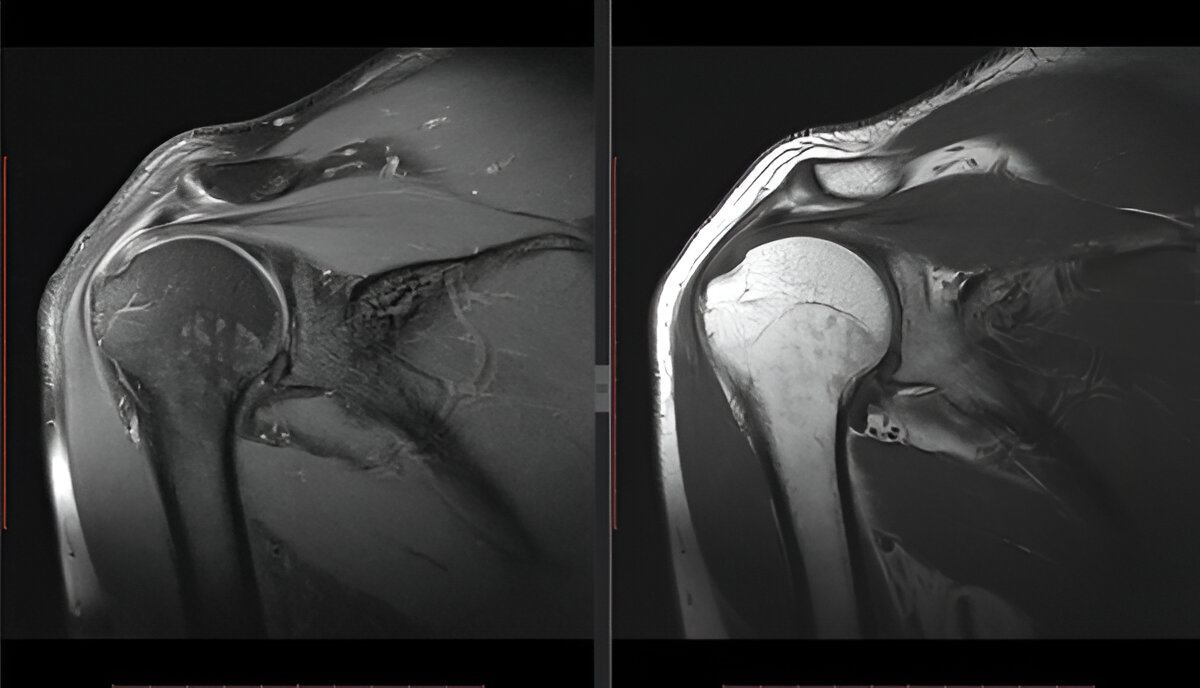

The Rotator Cuff: Stabilizers in Motion

The rotator cuff is a group of four muscles and tendons that stabilize the glenohumeral joint:

Supraspinatus

Infraspinatus

Teres minor

Subscapularis

These muscles keep the humeral head centered in the socket while allowing rotation and lifting.

The joint capsule encloses the glenohumeral joint, lined by the synovial membrane which secretes lubricating fluid.

Glenoid labrum – A ring of cartilage that deepens the socket for joint stability

Rotator cuff tears

These conditions often result from repetitive stress, trauma, or age-related degeneration.